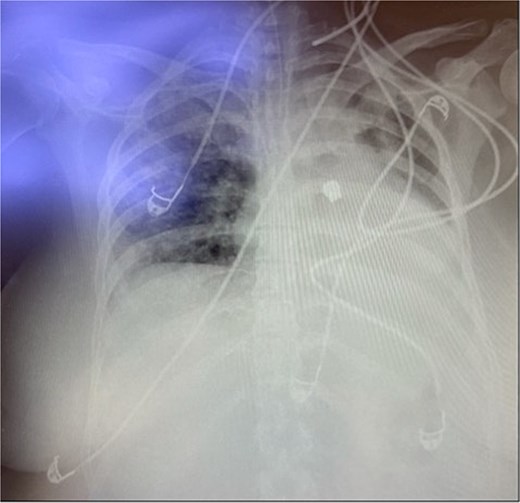

Throughout her 1-month hospitalization, she underwent two extubation trials, both of which were unsuccessful, necessitating reintubation. Extubation trials were unsuccessful due to weak respiratory muscles resulting from prolonged intubation and accumulation of secretions. After the second reintubation, a routine post-intubation chest X-ray incidentally revealed a FB located in the left middle zone of her left lung (Fig. 1). Despite this finding, the patient remained clinically stable with no significant changes in her oxygenation levels or ventilator parameters. The FB was suspected to be a dental bridge, likely aspirated during the second reintubation procedure.